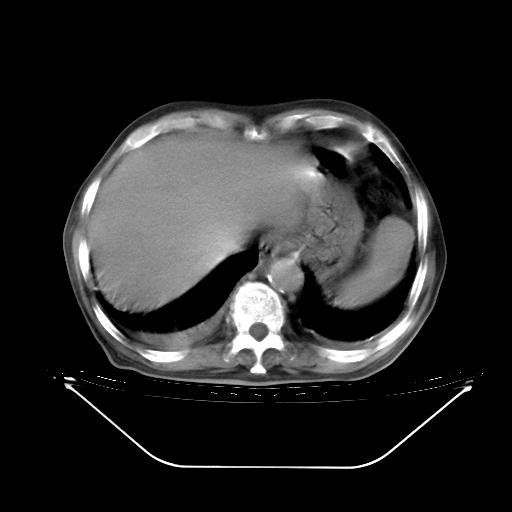

5月9日肺部CT(在4月27日齐鲁医院肺部CT描述部分肺组织磨玻璃样改变,12天后肺组织广泛磨玻璃样改变)

2009年5月9日肺部CT

大致读了系列胸部CT:纵隔窗无明显异常,肺窗:从4、27至今:主要是双肺中下野外带可见毛玻璃样改变,目前处于急性肺泡炎阶段,至于原因考虑1、结替组织或胶原血管性疾病所致?2、恶性疾病如恶组在肺部所致的表现或细支气管肺泡癌?3、药物或其它原因如肺蛋白沉着症所致肺泡炎目前不太可能?总之,明天就去请我院的呼吸科、感染科、血液科和临免专家会诊哈。